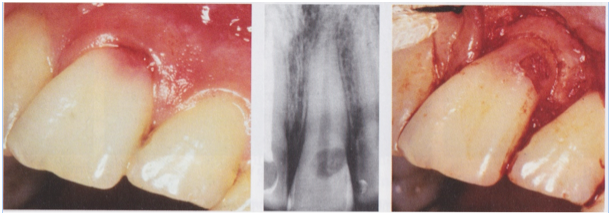

2- Attempt to remove the lesion in its entirety. The ultimate goal of treatment with ECIR lesions is to remove or inactivate all resorptive tissue. If this is not achieved, any clastic cells left behind will continue to do what they do best, destroy dentin. The compromised dentin and resorptive tissue is first debrided mechanically with a bur. Cases with small external pinpoint perforations can be accessed internally. Larger more cavernous perforations may require raising a flap for external surgical access (Figure 16) . A cotton pellet soaked in 90% Trichloracetic acid (TCA) is placed in the defect for at least one minute for the purpose of “burning out” any tissue and clastic cells that were not removed mechanically (Figure 17). The TCA causes any soft tissue contacted to undergo coagulation necrosis.

Figure 16- A sulcular incision is made and a flap raised to expose a Class III ECIR lesion on the facial of #8.

Figure 17- A cotton pellet soaked in 90% Trichloracetic acid is placed into the defect for one minute following mechanical debridement in an attempt to destroy all resorptive cells.

3-Restore the defect. A glass ionomer cement (Geristore) is the most commonly used restorative material for restoring ECIR defects (Figure 18). It is well tolerated by the periodontium when placed subgingivally and its dual cure action provides an immediate seal, unlike MTA, which has a risk of washing out due to a longer setting time. Geristore is also more esthetically acceptable and can easily be veneered with composite when necessary. The TCA has a strong demineralization effect on dentin and results in a surface that does not bond well. After using TCA, it is advised to remove a superficial layer of dentin with a slow round bur prior to etching, bonding, and restoring.

Figure 18 – The ECIR defect is resored with Geristore and the tissue reflected back into place and sutured. The image on the right shows a 6 month recall with healthy periodontium.